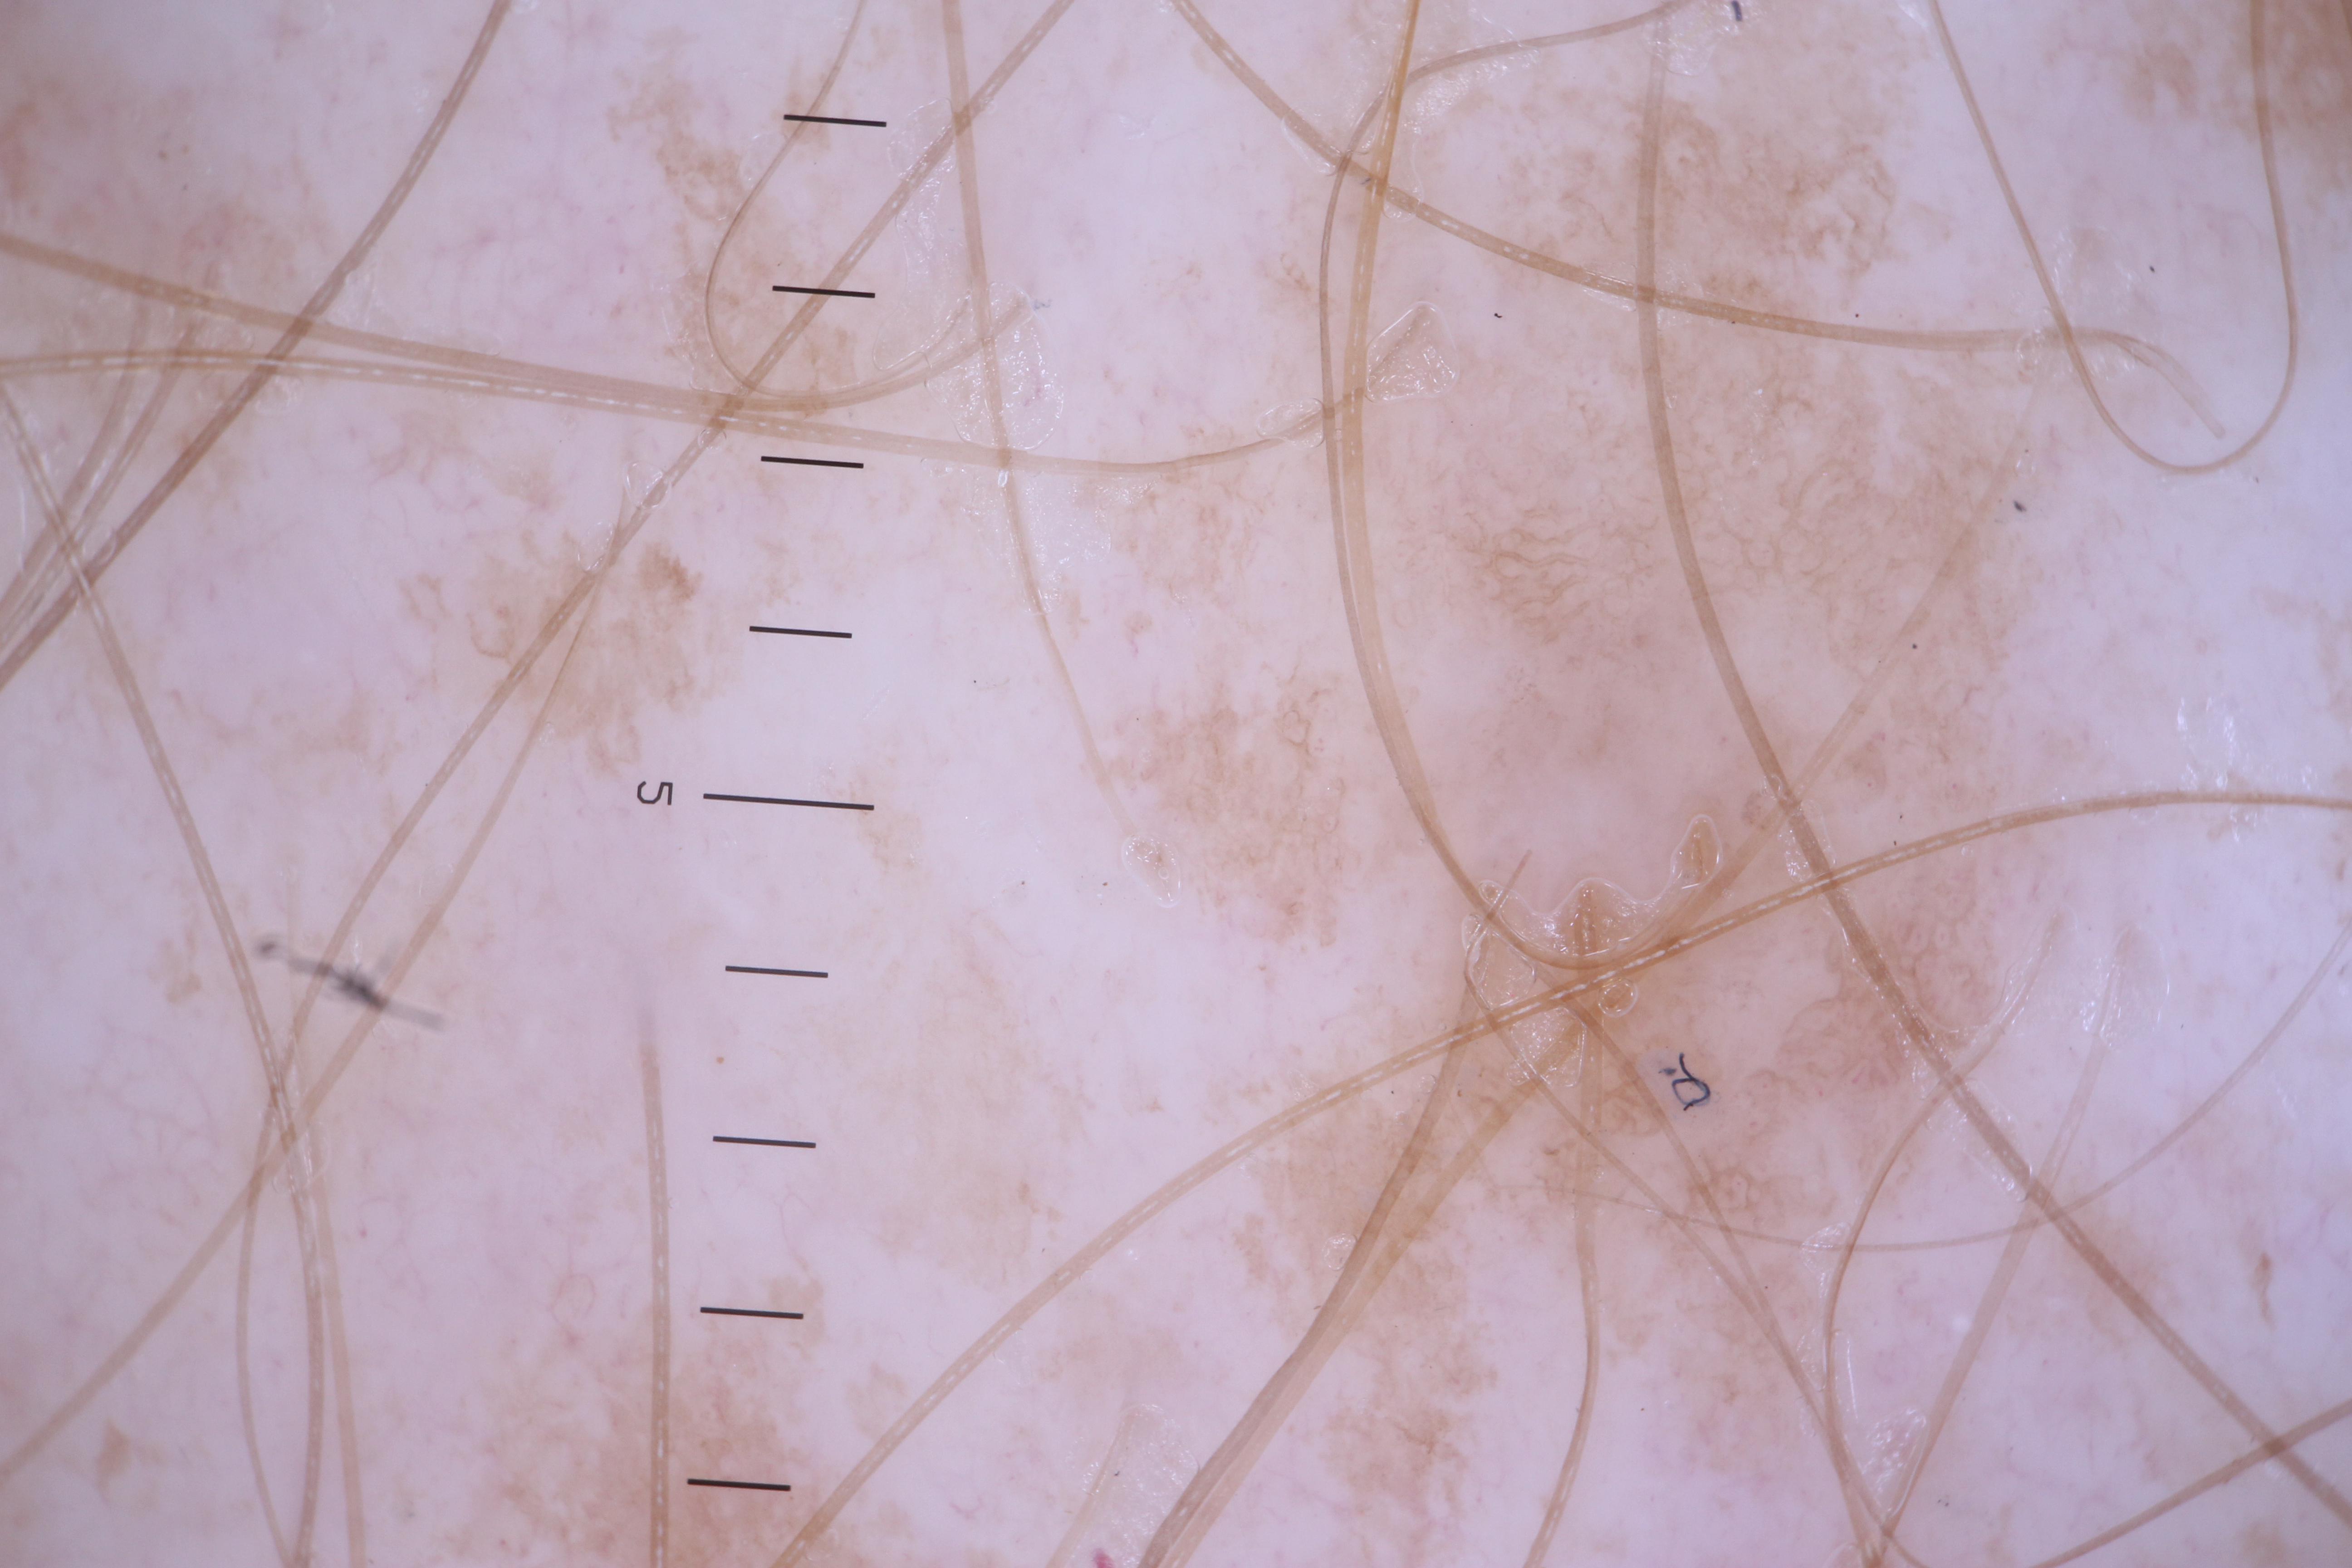

{

"age_approx": 65,

"anatom_site_general": "upper extremity",

"concomitant_biopsy": false,

"diagnosis_1": "Benign",

"diagnosis_confirm_type": "serial imaging showing no change",

"fitzpatrick_skin_type": "II",

"image_type": "dermoscopic",

"lesion_id": "IL_9283481",

"patient_id": "IP_6326286",

"sex": "female"

}